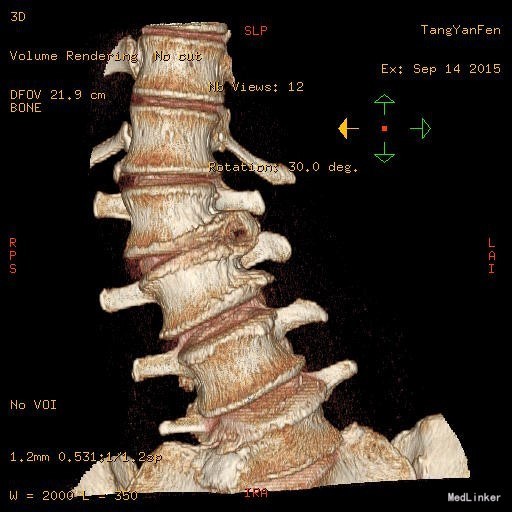

主诉:右下肢麻木11年,腰部酸痛无力 现病史:女性患者,65岁,患者于11年前无明显诱因下出现右下肢麻木,自大腿至右踝部,站立位加重。未予重视,后期出现腰臀部僵硬,弓背僵硬无力,自主行走距离不足200米,曾于06年经X线平片及MRI检查:腰椎椎管狭窄伴有腰椎滑脱,椎间盘突出等。

查体:侧弯畸形,右臀部及右下肢麻木疼痛,腰部活动受限,难以站立。右侧支腿抬高试验60°。双下肢肌力肌张力可。 辅助检查:平片:腰椎侧弯,椎体滑脱,曲度后凸 磁共振:L2-3,L4-5,L5-S1腰椎椎管狭窄,l2-3L3-4L4-5L5-S1腰椎间盘突出,腰椎退变

诊断: 腰椎侧弯,腰椎间盘突出 治疗:1期微创侧路椎体融合术+2期 微创后路经皮内固定术